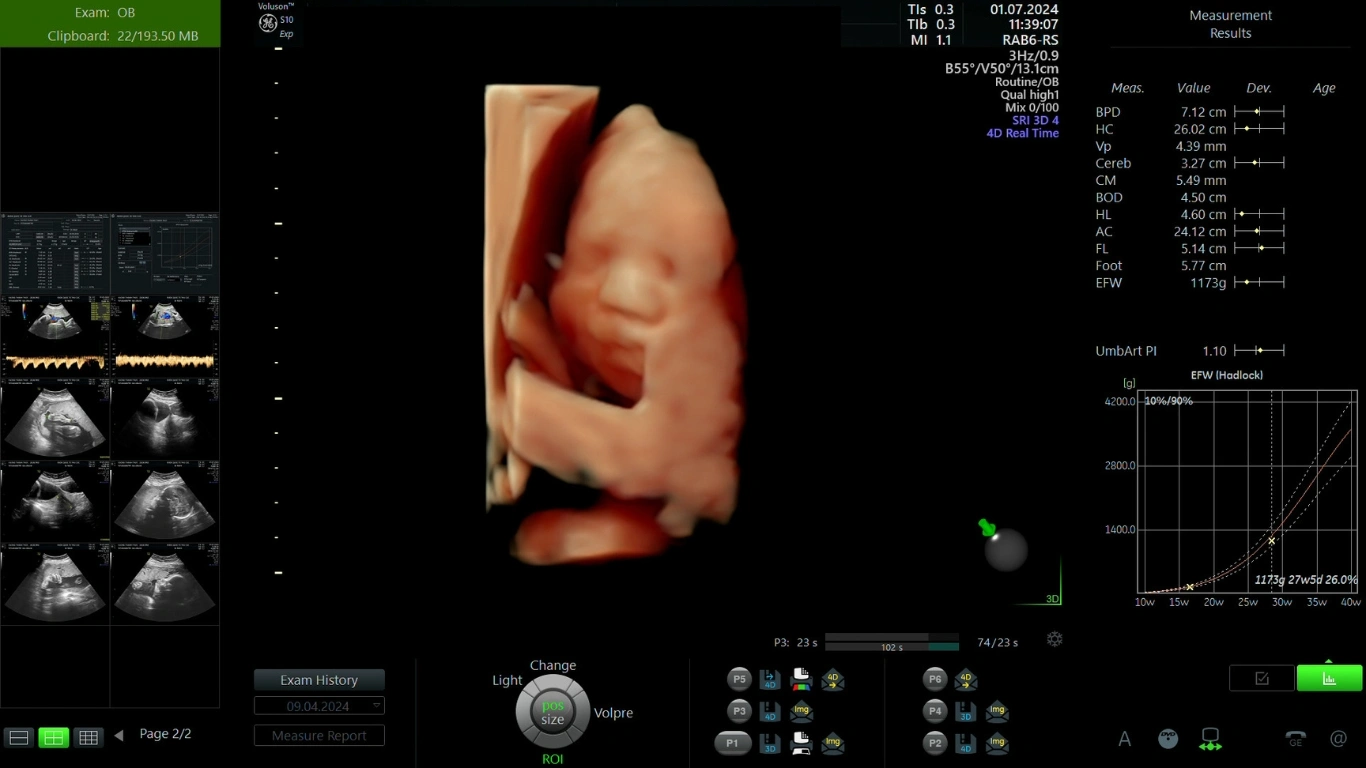

Tuần thứ 24 của thai kỳ là thời điểm cha mẹ đã có thể nhìn ngắm nhìn những hình ảnh siêu âm 4D thai 24 tuần rõ nét. Đây cũng là công cụ hữu ích để bác sĩ thực hiện khảo sát hình thái học, đánh giá các chỉ số sinh tồn quan trọng của bé.

Giá trị lớn nhất của hình ảnh siêu âm 4D thai 24 tuần không chỉ nằm ở cảm xúc gắn kết mà còn giúp bác sĩ đánh giá chính xác hơn chức năng vận động và sàng lọc dị tật một cách hiệu quả.

Khi nhận kết quả siêu âm, mẹ dễ dàng thấy một loạt các ký hiệu và con số. Đây là những chỉ số sinh trắc học giúp đánh giá sự phát triển cân đối của thai nhi 24 tuần.

Dưới đây là bảng tham chiếu các chỉ số quan trọng mà mẹ có thể đối chiếu. Lưu ý rằng các chỉ số này là một khoảng giá trị, sự chênh lệch nhỏ thường không đáng lo ngại.

| Chỉ Số | Khoảng Tham Chiếu Chuẩn | Ý Nghĩa Y Khoa |

| Đường kính lưỡng đỉnh (BPD) | 53 – 65 mm | Đo khoảng cách rộng nhất giữa hai xương đỉnh sọ, phản ánh sự phát triển của não bộ. |

| Chu vi vòng đầu (HC) | 204 – 239 mm | Đo chu vi vòng đầu, kết hợp với BPD để đánh giá toàn diện kích thước đầu của bé. |

| Chu vi vòng bụng (AC) | 171 – 231 mm | Đo chu vi vòng bụng, cho thấy sự phát triển của các cơ quan nội tạng và tình trạng dinh dưỡng. |

| Chiều dài xương đùi (FL) | 39 – 47 mm | Đo xương dài nhất cơ thể, phản ánh tốc độ phát triển chiều dài của thai nhi. |

Giai đoạn thai 24 tuần được xem là "thời điểm vàng" để khảo sát hình thái vì thai nhi đã đủ lớn, các cơ quan hình thành rõ nét và lượng nước ối dồi dào tạo điều kiện quan sát lý tưởng. Siêu âm 4D ở mốc này có thể phát hiện chính xác 80-85% các dị tật cấu trúc lớn.